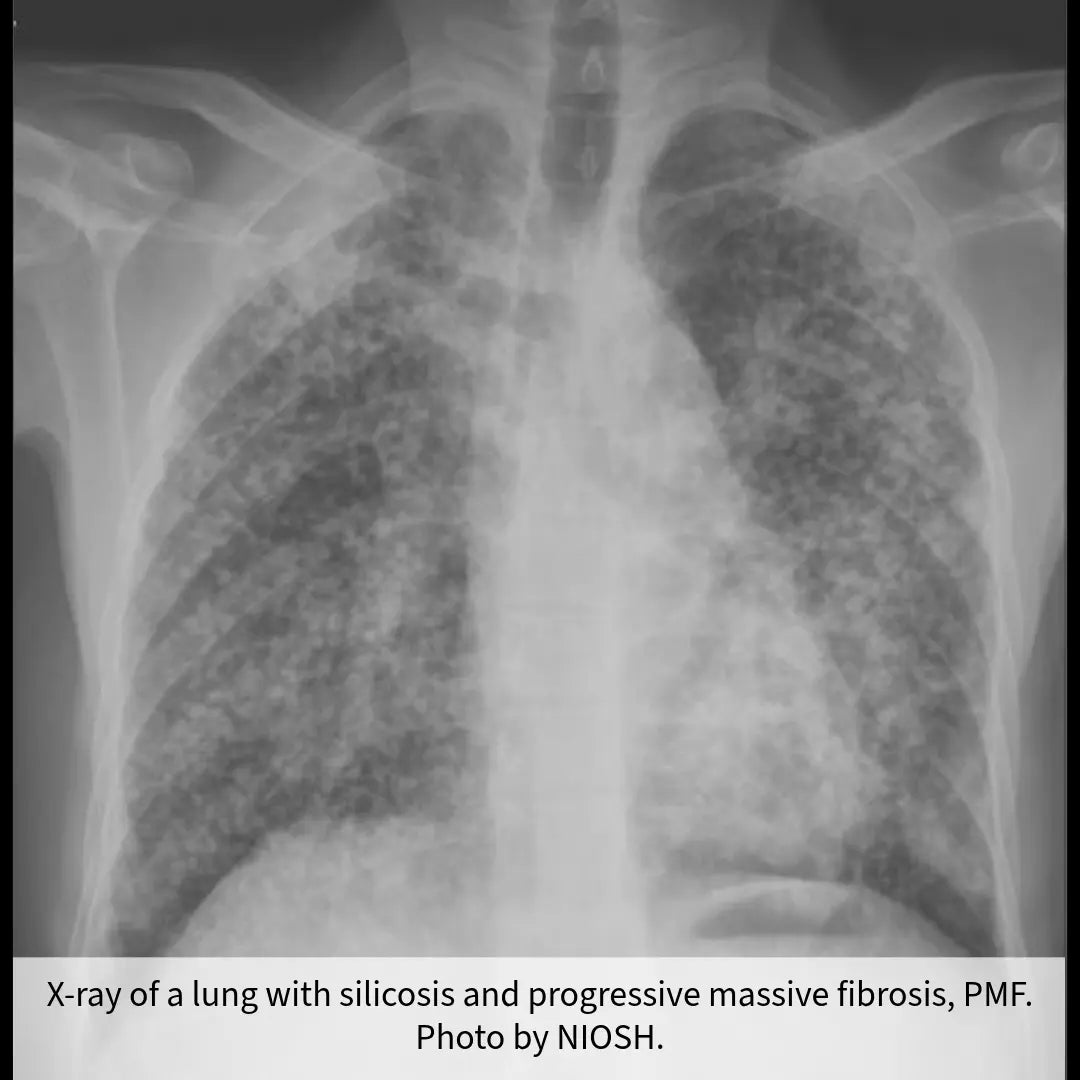

Recent OSHA Activity in the Stone Industry

Aug 30, 2024 | Dolan Williams, CSHOIn a stark reminder of the serious health risks associated with silica dust exposure, the Occupational Safety and Health...